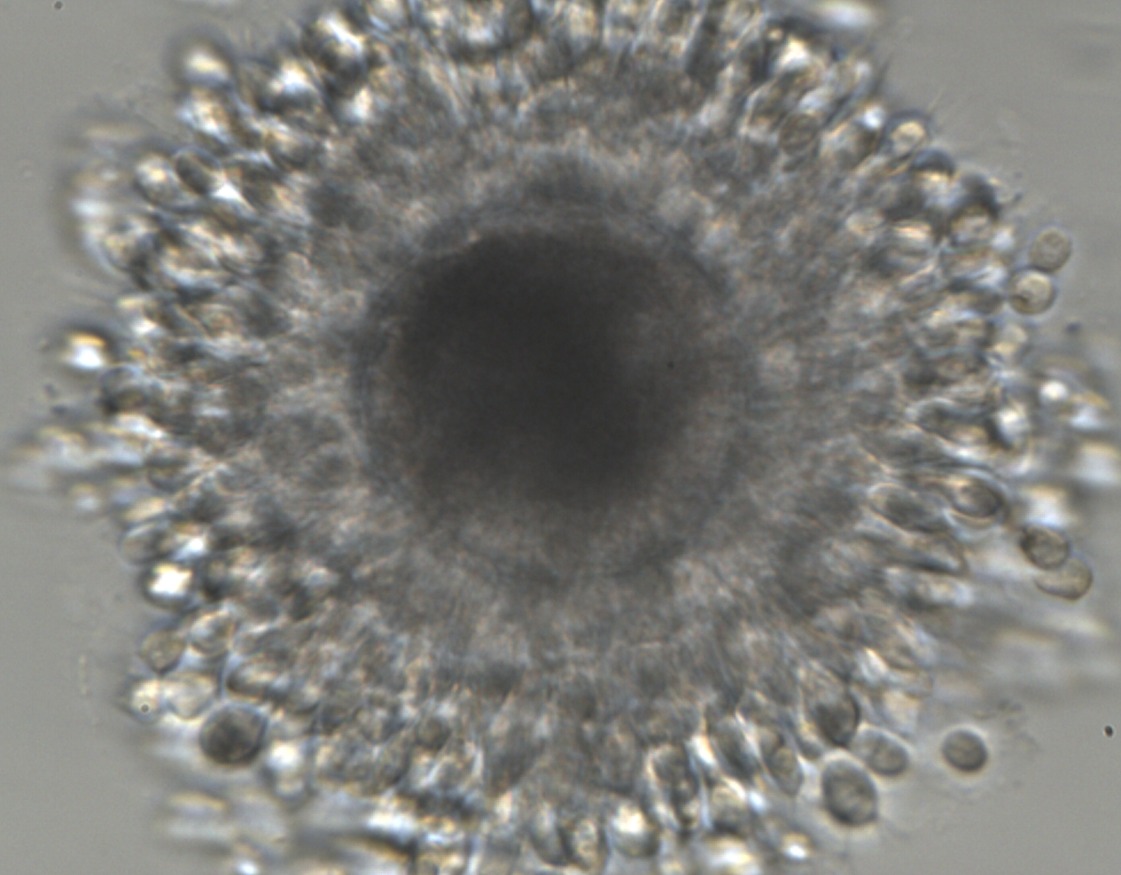

In vitro maturation is a laboratory technique that allows immature oocytes, recovered by follicular aspiration, to mature outside the mare’s body. This process involves retrieving these immature oocytes from the ovaries and placing them in a specialized culture medium that supports their growth and development. Over a specific period, the oocytes progress through the final stages of maturation until they reach the matured stage, necessary for fertilization. After the maturation period, the oocytes are analyzed and prepared for the Intracytoplasmic Sperm Injection (ICSI) in our Laboratory. Each phase of the process is meticulously executed by highly trained embryologists. Their extensive experience ensures precision, contributing to the optimal development and potential success of the in vitro procedures.